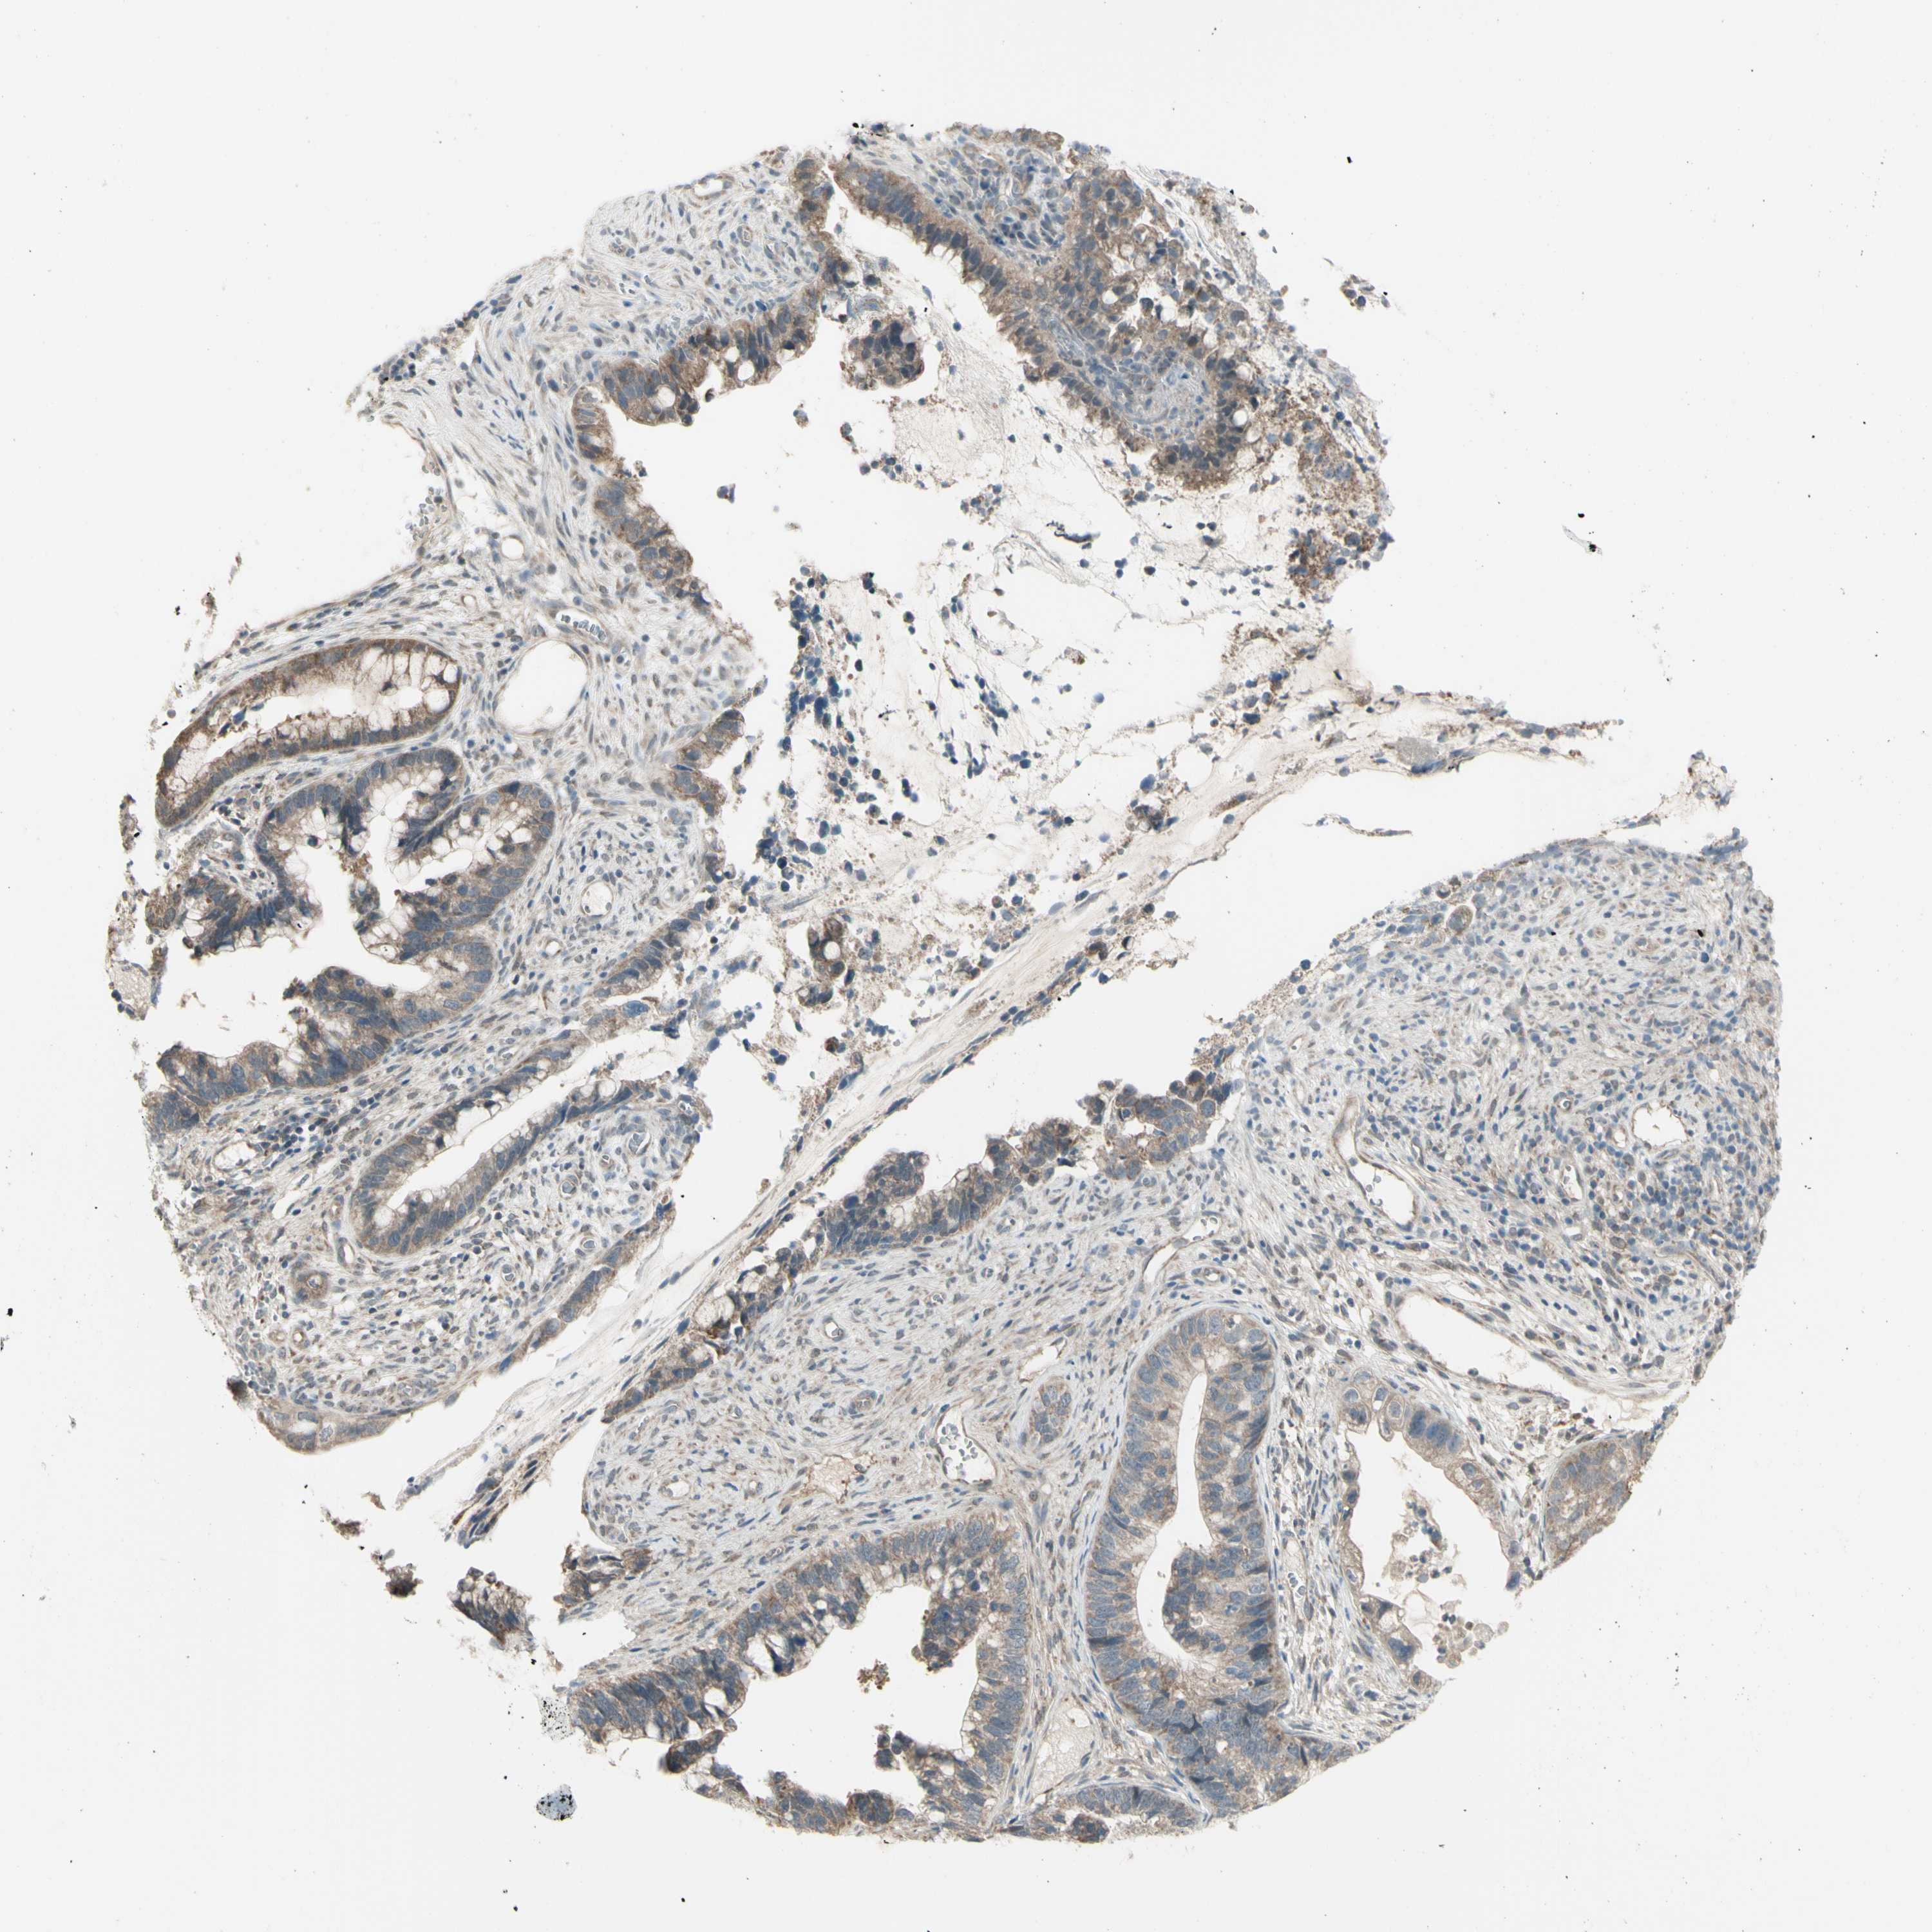

CERVICAL CANCER - Protein expressioni

A mouse-over function shows sample information and annotation data. Click on an image to view it in a full screen mode. Samples can be filtered based on level of antibody staining by selecting one or several of the following categories: high, medium, low and not detected. The assay and annotation is described here.

Note that samples used for immunohistochemistry by the Human Protein Atlas do not correspond to samples in the TCGA dataset.

Antibody stainingi

Antibody staining in the annotated cell types in the current human tissue is reported as not detected, low, medium, or high, based on conventional immunohistochemistry profiling in selected tissues. This score is based on the combination of the staining intensity and fraction of stained cells.

Each image is clickable and will lead to virtual microscopy that enables deeper exploration of all samples and also displays staining intensity scores, fraction scores and subcellular localization as well as patient and tissue information for each sample.

Antibody HPA010551

Staining

High

Medium

Low

Not detected

Intensity

Strong

Moderate

Weak

Negative

Quantity

>75%

75%-25%

<25%

None

Location

Nuclear

Cytoplasmic/membranous

Cytoplasmic/membranous,nuclear

Squamous cell carcinoma, NOS

Adenocarcinoma, NOS